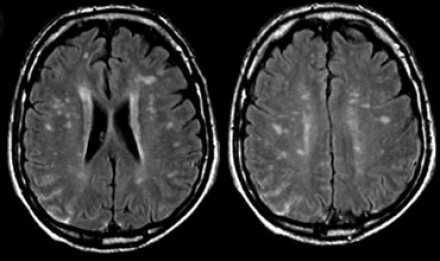

Вернемся снова к первому случаю: на МР-томограммах выявлены очаговые изменения, и сейчас они гораздо более очевидны. Имеет место распространенное вовлечение глубоких отделов полушарий, однако дугообразные волокна и мозолистое тело остаются интактными. Нарушения ишемического характера в белом веществе могут проявляться как лакунарные инфаркты, инфаркты пограничной зоны или диффузные гиперинтенсивные зоны в глубоком белом веществе.

Лакунарные инфаркты возникают в результате склероза артериол или мелких пенетерирующих медуллярных артерий. Инфаркты пограничной зоны возникают в результате атеросклероза более крупных сосудов, например, при каротидной обструкции или вследствие гипоперфузии.